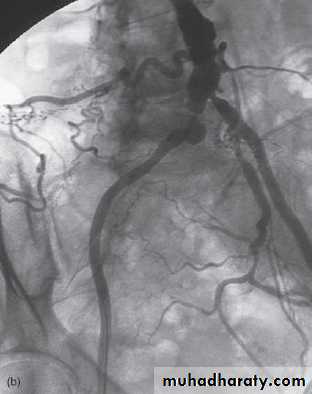

Digital subtraction angiography

Digital subtraction is a process whereby a computer removes unwanted information from a radiographic image. Digital subtraction is particularly useful for angiography, referred to as DSA.

Mask image contrast image subtracted image